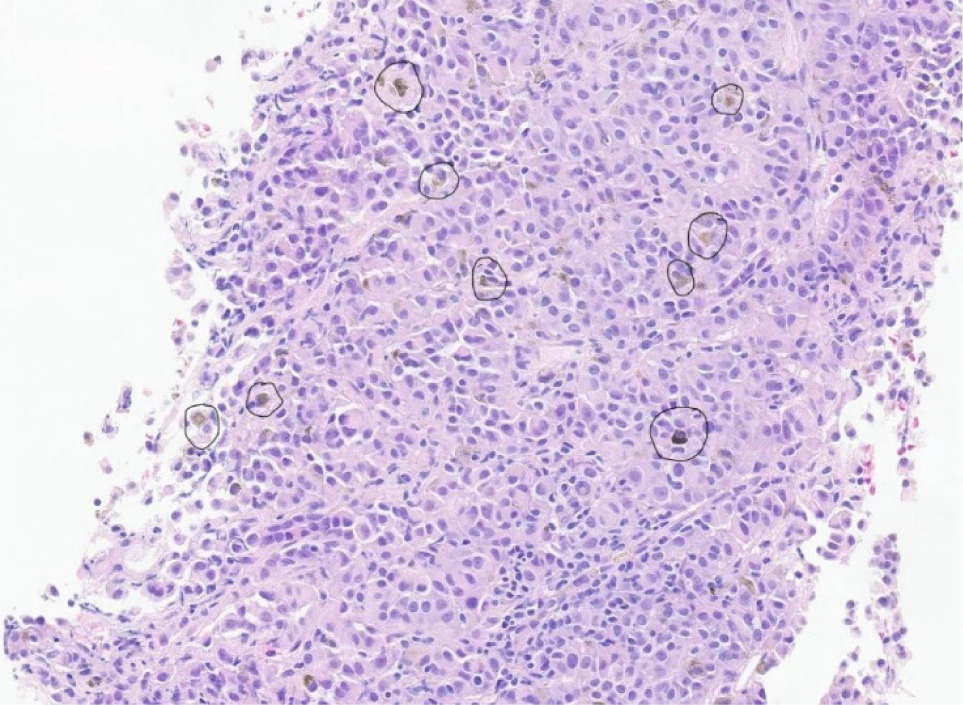

The patient was initially diagnosed with a tumor of the choroid of the right eye, identified pathologically by immunohistochemistry as malignant melanoma. MRI of the abdomen at the time of diagnosis showed the liver, kidneys, and adrenals were within normal limits. The patient was treated with plaque brachytherapy, 21 seeds and an 18 mm plaque left in for 4 days. The patient remained in remission for 9 years until the detection of a 1.5 cm soft tissue nodule in the anterior upper pole of the left kidney on routine surveillance imaging. The patient presented with no symptoms, no hematuria, flank pain, or weight loss. Whole body PET-CT scan showed no other suspicious lesions, and physical exam revealed no cutaneous lesions. Recurrence of melanoma to the left kidney was confirmed, and renal cell carcinoma (RCC) was ruled out by percutaneous renal mass biopsy (Figure 1). After consultation with urology and surgical departments, and medical oncology, the decision was made to pursue surgical removal of this solitary melanoma metastasis. The tumor was of low complexity, with a RENAL score of 6 (R1 E3 N1 L1), for which AUA guidelines indicate PN to be appropriate (19). The patient underwent robotic partial nephrectomy with final pathology confirming melanoma with immunochemistry positive for SOX-10 (20). PN had the same level of difficulty as a nonmelanoma renal mass of similar size. The operative time was 2.5 h, and the length of hospital stay was 3 days. To date, the patient has been monitored with serial imaging every 6 months. No adjuvant systemic therapy was given post-nephrectomy, as the patient had no other evidence of disease at that time, and systemic options for ocular melanoma are limited.

Figure 1: Small renal mass in the upper pole of the left kidney as seen on CT and MRI. (A) Axial view from CT demonstrates a 12 mm lesion. (B) Coronal view from the abdominal MRI also shows a solitary 12 mm upper pole anterior endophytic lesion of the left kidney. Pathology indicates metastatic ocular melanoma.